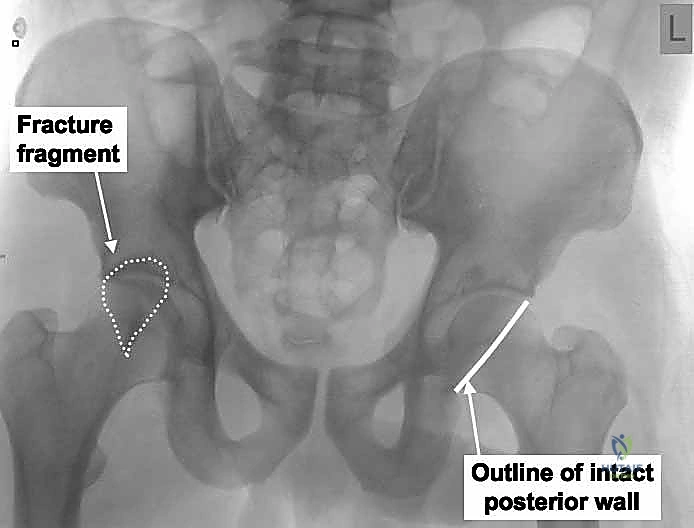

2. التصوير بالأشعة السينية (X-rays)

هي الخطوة الأولى. يتم أخذ صورة أمامية خلفية (AP) للحوض. ولكن في كسور الحُق، هذه الصورة لا تكفي. يتم طلب صور بوضعيات خاصة تُعرف بـ مناظر جوديت (Judet Views):

* المنظر المائل السدادي (Obturator Oblique): يوضح العمود الأمامي والجدار الخلفي.

* المنظر المائل الحرقفي (Iliac Oblique): يوضح العمود الخلفي والجدار الأمامي.

- الأعمدة الأمامية والخلفية (Anterior & Posterior Columns): تشكل هذه الأعمدة الدعامات الهيكلية الأساسية التي يحمل عليها الحُق. في حالة "كسور الجدار الخلفي النقي"، يظل العمود الخلفي سليماً وقائماً، وهذا عامل تمييزي حاسم يساعد الجراح في التشخيص واختيار النهج الجراحي.

- الجدران الأمامية والخلفية (Anterior & Posterior Walls): هذه الجدران تمثل الحواف العظمية التي تحيط بالتجويف وتمنع رأس الفخذ من الانزلاق أو الخلع. تركيزنا في هذا الدليل ينصب على الجدار الخلفي، وهو الحافة الخلفية للتجويف، والذي يعتبر السد المنيع ضد خلع الورك للخلف (وهو النوع الأكثر شيوعاً للخلع).